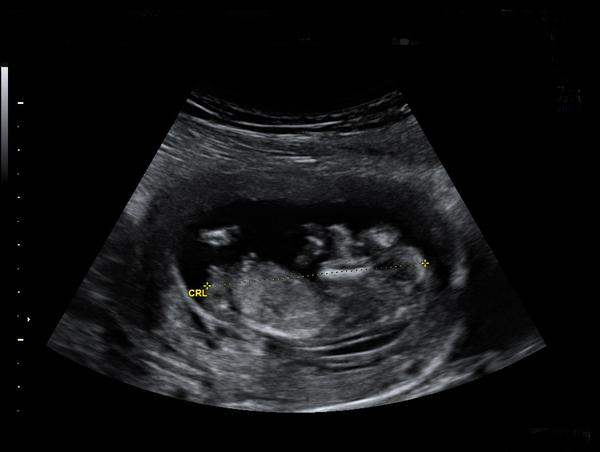

tak to jo - tak to vypadá vážně na chlapečka. Jak jsou hubený tak je maj prostě velký :D Kdyby to byla fotka z 12-13 tt tak by to vypadalo na holčičku (jednalo by se o pohlavní hrbolek který je rovnoběžný s páteří) ale v 17 to už bude pinďa , a mám dojem že vidím i varlátka.

(jinak jak je napsáno CRL tak to je kostrč - na druhé straně pak logicky hlava :D no a nad tím CRL ten výběžek o dvou jakoby čárečkách je ten pohlavní hrbolek na základě čeho se určuje pohlaví okolo toho 12 tt. )